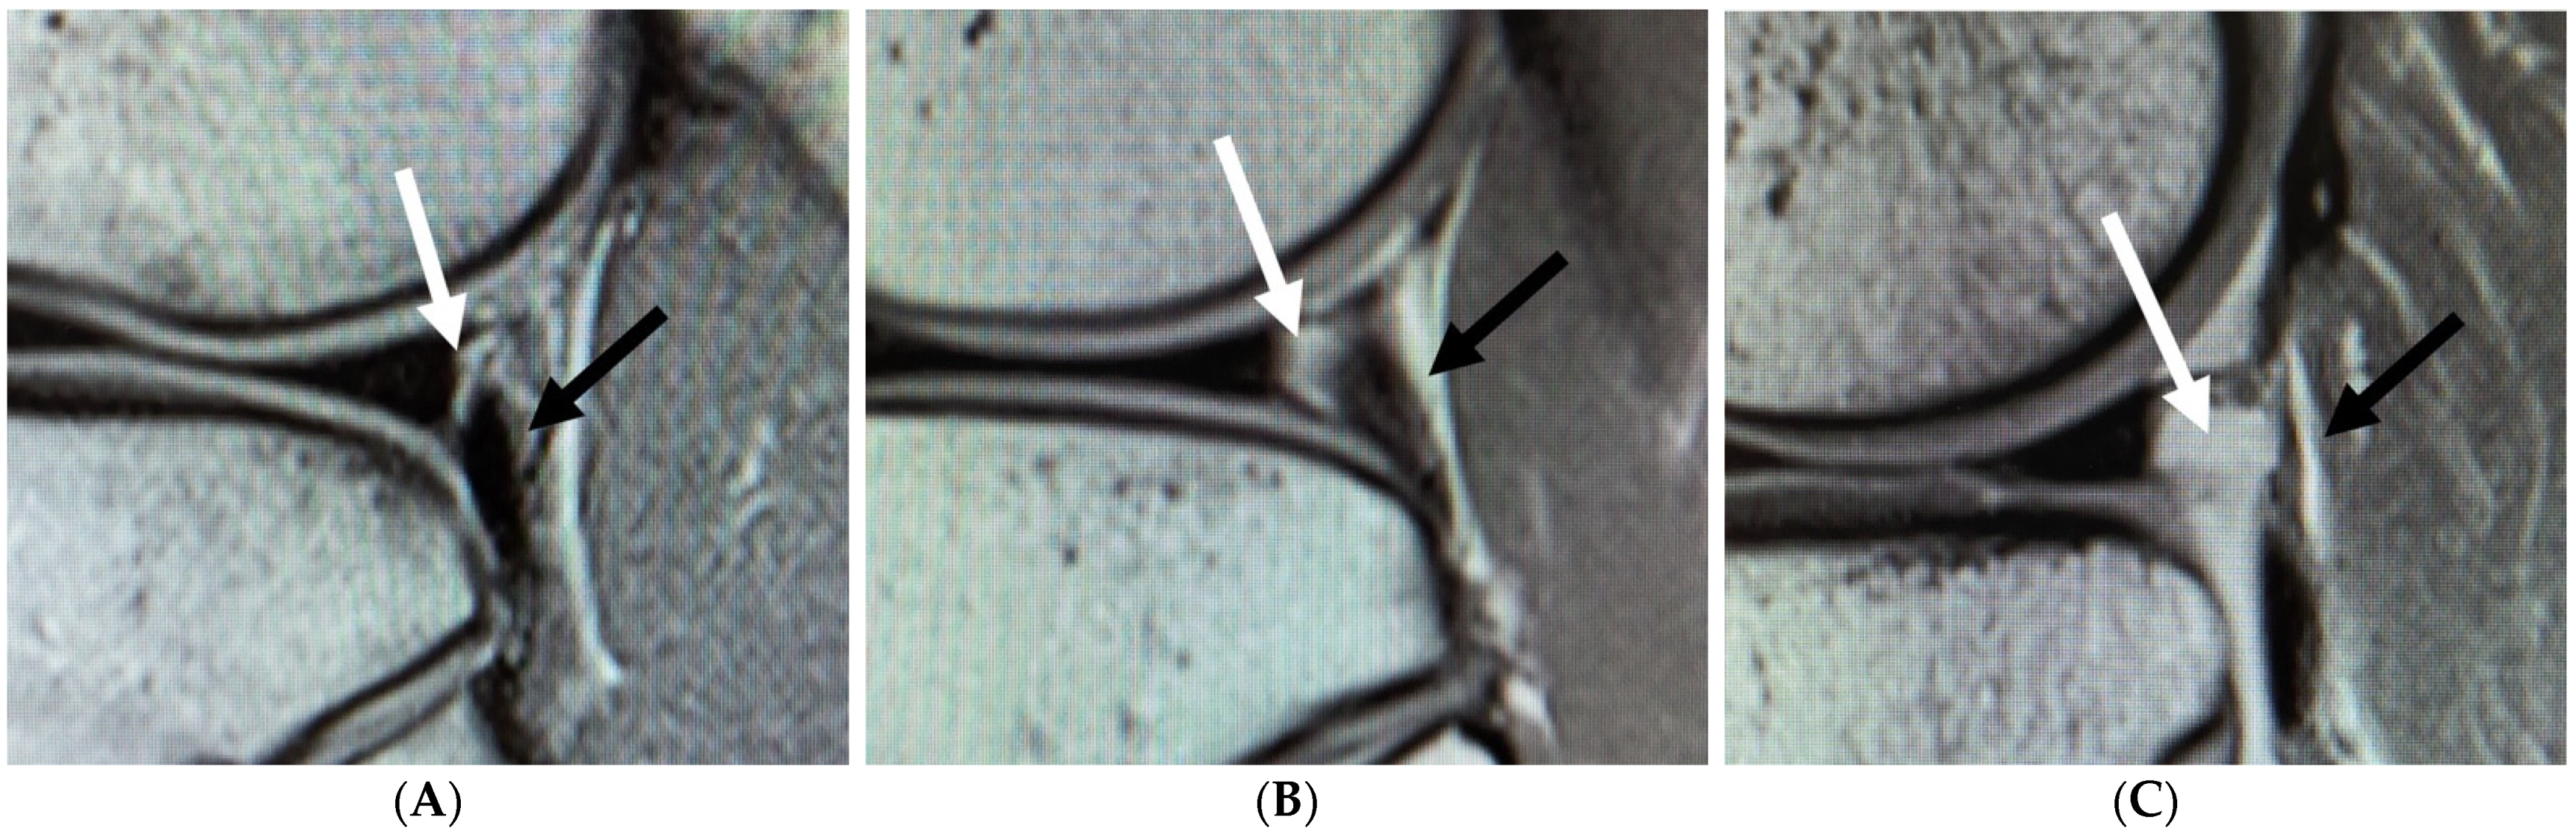

2.2. MRI Measurement

- Suganuma, J.; Mochizuki, R.; Inoue, Y.; Yamabe, E.; Ueda, Y.; Kanauchi, T. Magnetic resonance imaging and arthroscopic findings of the popliteomeniscal fascicles with and without recurrent subluxation of the lateral meniscus. Arthroscopy 2012, 28, 507–516. [Google Scholar] [CrossRef] [PubMed]

- Shin, H.K.; Lee, H.S.; Lee, Y.K.; Bae, K.C.; Cho, C.H.; Lee, K.J. Popliteomeniscal fascicle tear: Diagnosis and operative technique. Arthrosc. Tech. 2012, 1, e101–e106. [Google Scholar] [CrossRef]

- Zheng, J.; Xiao, Q.; Wu, Q.; Deng, H.; Zhai, W.; Lin, D. Tears of the Popliteomeniscal Fascicles of the Lateral Meniscus: An Arthroscopic Classification. Cartilage 2020, 2020, 1947603520980156. [Google Scholar] [CrossRef]

- Sakai, H.; Sasho, T.; Wada, Y.; Sano, S.; Iwasaki, J.; Morita, F.; Moriya, H. MRI of the popliteomeniscal fasciculi. AJR Am. J. Roentgenol. 2006, 186, 460–466. [Google Scholar] [CrossRef] [PubMed]